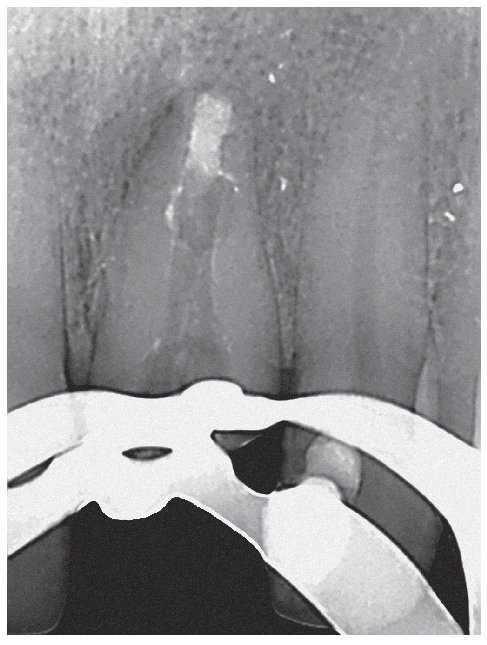

Figura 4a. La radiografía diagnóstica muestra una obturación con sellado marginal en sentido mesiodistal.

Figura 4b. Situación clínica después de retirar la prótesis que necesitaba ser rehabilitada: el conducto radicular muestra un tramo largo ovalado en sentido vestibulolingual, lo que no se reflejó en la radiografía. El cono central existente sólo ocupa una pequeña parte del conducto radicular en sentido horizontal. Se observan algunos restos de sellador y mucho tejido necrótico en la luz residual.